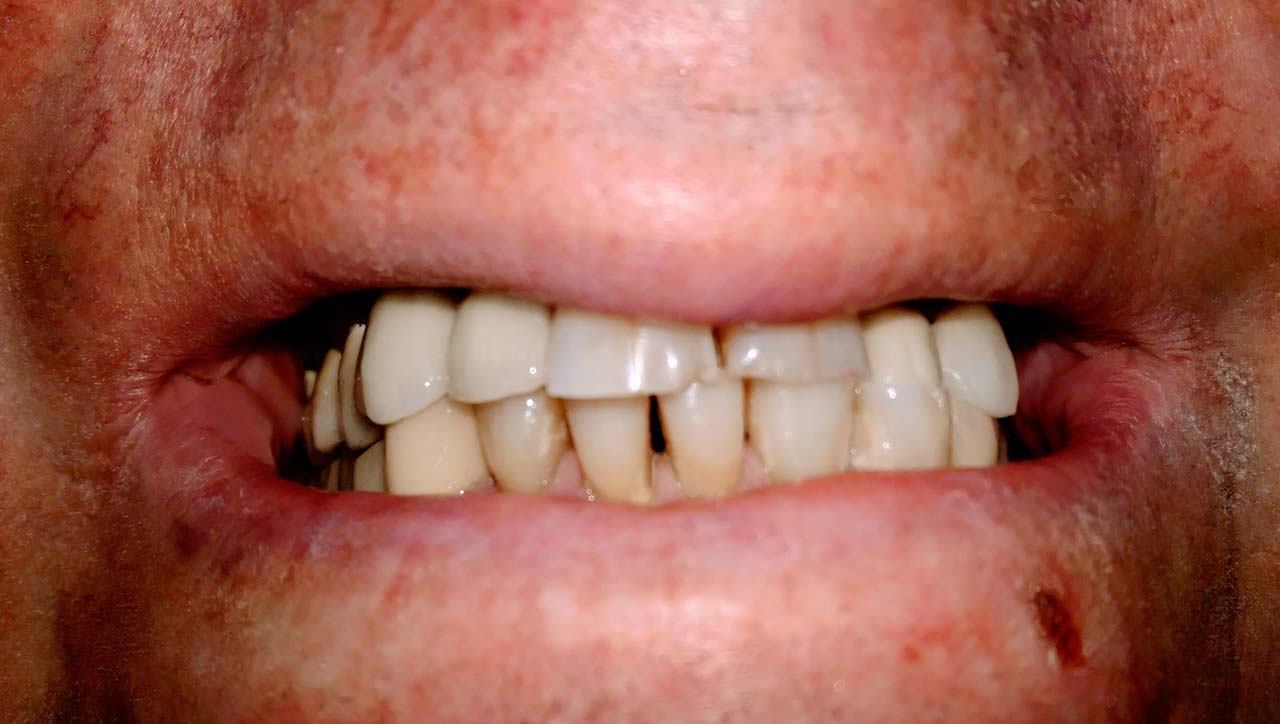

Elhanyagolt fogsor cseréje 2 nap alatt

2 nap alatt varázsoltuk ezt a szép esztétikus alsó, felső körhídat implantátumokkal megtámasztva a korábban elhanyagolt szájba. Az 1. nap 26 fogat távolítottunk el, mert annyira rossz állapotban voltak, és rögtön azonnal terhelhető IHDE svájci implantátumokat raktunk be, fentre 8, lentre 6 darabot. A sebeket összevarrtuk és intraorális szkennerrel digitális lenyomatot vettünk. 2 nap múlva pedig beragasztottuk a kész PMMA műanyag körhidakat. Dr. Kelemen Péter és a Symbion Fogtechnika munkája.